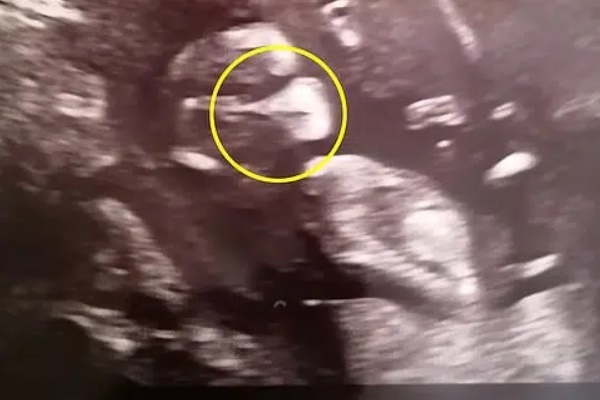

Vợ chồng chị Sarah Beeston, đến từ Hawaii (Mỹ), cũng giống như vậy. Họ luôn mong chờ đến từng kỳ siêu âm để được xem hình hài của con. Song, họ đã vô cùng thất vọng khi nghe bác sĩ nói rằng em bé không có tóc vì trên hình ảnh siêu âm hoàn toàn không nhìn thấy một sợi tóc nào, dù vợ chồng chị Sarah ai cũng có mái tóc dày vàng óng.

Tuy nhiên, khi Jack Paul Beeston chào đời, cả bố mẹ lẫn e-kíp đỡ sinh đều phải kinh ngạc khi cậu bé được sở hữu một mái tóc dày vàng óng như mẹ và đặc biệt là hiếm thấy ở trẻ vừa chào đời. Thậm chí, chị Sarah còn gói gọn cảm giác khi ấy bằng một từ "Sốc!". Bởi vợ chồng chị đã chuẩn bị tinh thần để chào đón con trai Jack "hói đầu".

Mặc dù trước đó bác sĩ siêu âm đã cảnh báo là có thể em bé bị hói đầu.

Tuy nhiên, tóc có thể mọc như "um tùm" cỏ dại, nhưng cũng có thể chúng chỉ mọc một chút vào cuối thai kỳ. Điều này có nghĩa là không phải lúc nào bác sĩ siêu âm cũng nhìn thấy chính xác bộ tóc của trẻ.